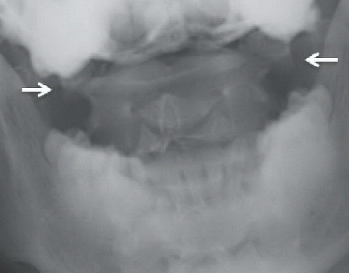

A fracture’s size and location are mostly determined with the aid of an X-ray. A CT scan is also recommended by the doctor to check for vertebral misalignment.

A computed tomography (CT) scan is a specialized X-ray that uses computer technology to produce slices through the target area. These incredibly precise images often show soft tissue injuries like ligament damage.